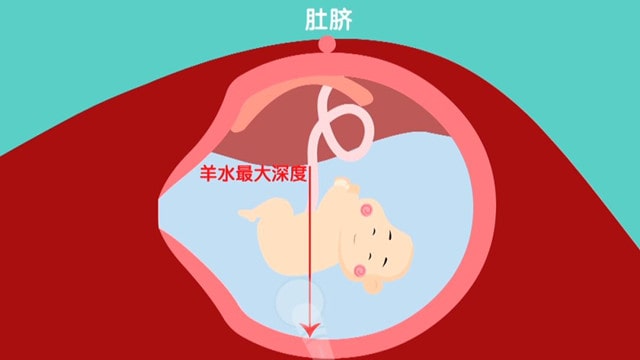

[胎儿发育]产检测量和计算羊水深度的时候,一般是以肚脐为圆心,把肚子里画一个十字,将腹部分成四个象限。 医生通过超声的探头,分别测量四个象限羊水最深的地方有多深,这样就得到了4个数值,

[胎儿发育]正常羊水指数是80-240mm,羊水指数<50mm为羊水过少,羊水指数>250mm为羊水过多。在门诊进行产检时,B超医生在进行B超检查,关于羊水的报告数值有两个,一个是羊水指数,另一个是羊水最大